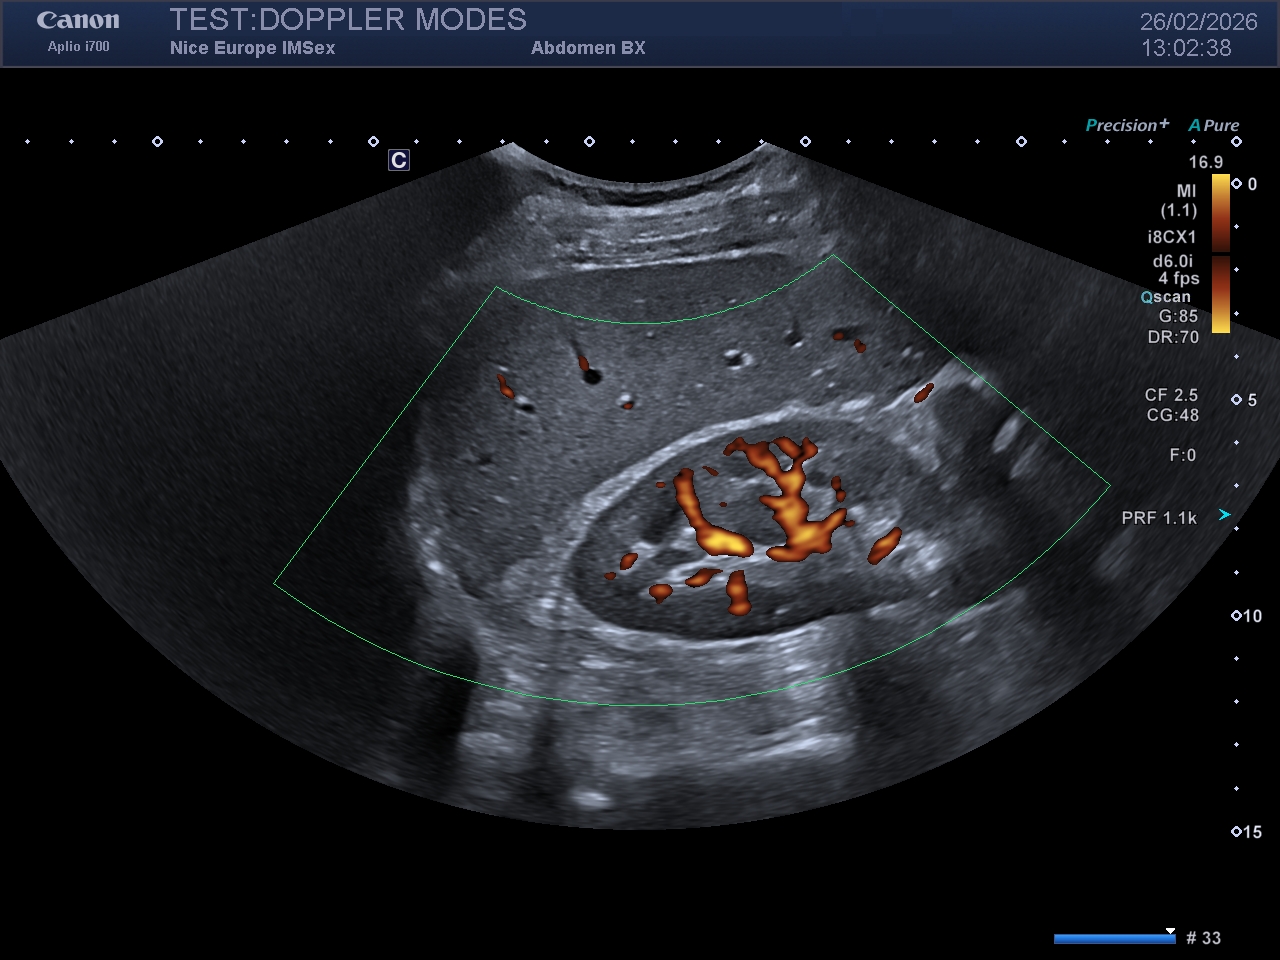

Légende : Image en Doppler couleur d'un rein droit

Légende : Image en Doppler Énergie du même rein droit. Notez la plus grande quantité de signal Doppler affichée sur l'image, mais aussi le caractère "grossier" de la cartographie couleur